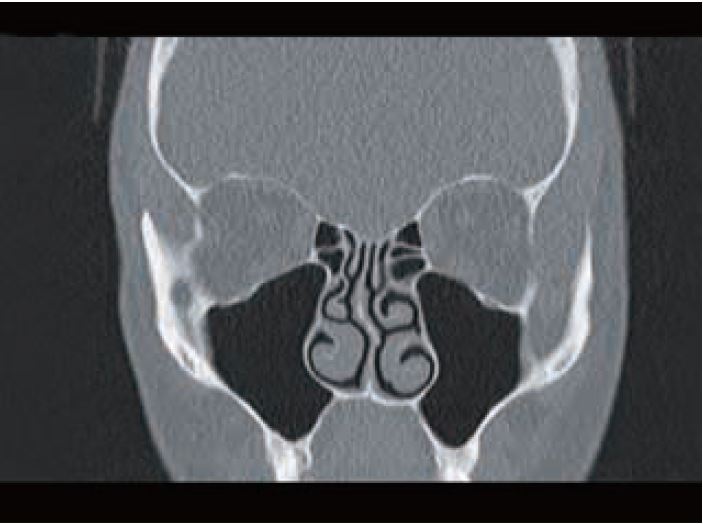

З наявною технологією зменшення дози, включаючи ітераційну реконструкцію AIDR 3D, у поєднанні з новими стандартами ефективності детектора, цілком можливо проводити КТ діагностичної якості з дозою, еквівалентною стандартному рентгенівському обстеженню. Звичайно, ці КТ з надзвичайно низькою дозою наразі не підходять для низькоконтрастних зображень, але вони цілком достатні та набагато перевершують набір рентгенограм для багатьох клінічних показань, що включають висококонтрастне окреслення. Попередні обмеження екстремального фотонного голодування просто більше не застосовуються (рис. 11,12).

Рис. 11 КТ грудної клітки з ультранизькою дозою. 0,1 мЗв - 35- річна жінка. Голка у лівому головному бронху. DLP 6

Рис. 12 КТ верхньощелепної пазухи. 0,02 мЗв – жінка 60 років. Доза: DLP 8,9